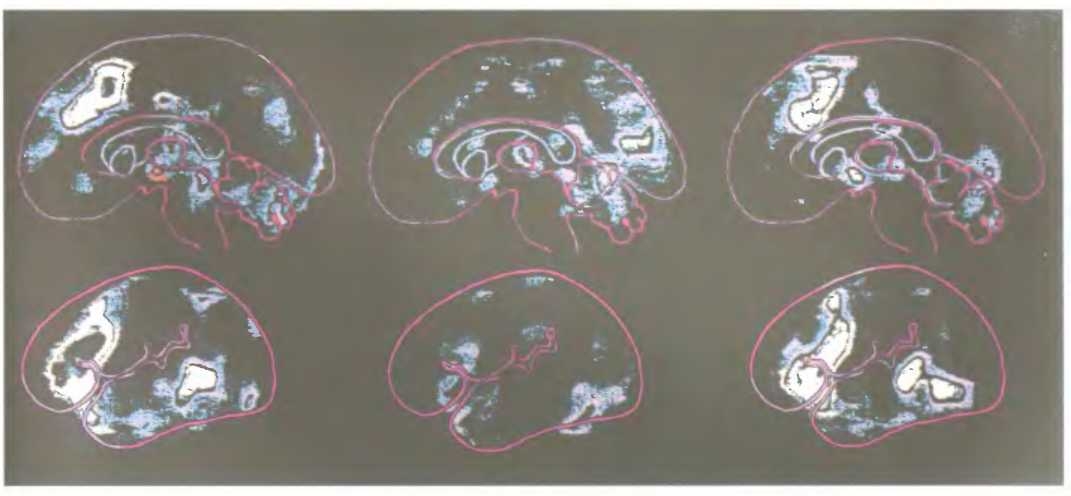

В результате некоторых повреждений мозга люди перестают замечать половину окружающего мира и игнорируют все, что находится с одной стороны (обычно слева) от центральной линии поля зрения. Справа показаны результаты попыток пациента, страдающего этим расстройством, воспроизвести рисунки, показанные слева.